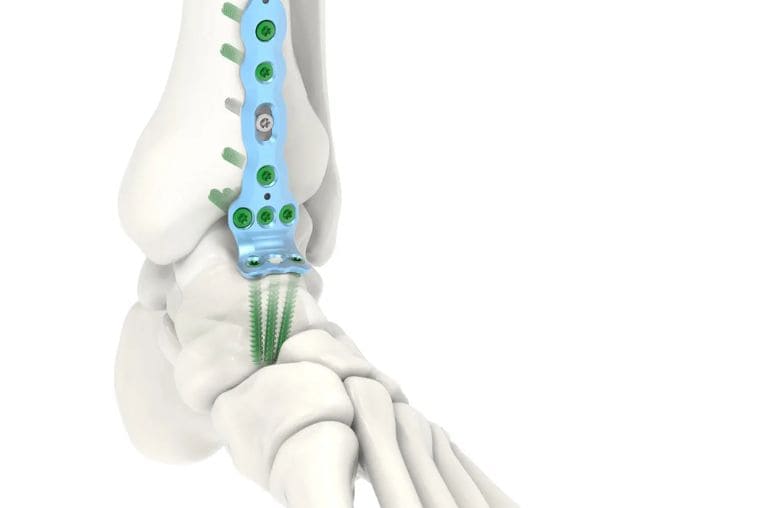

A cirurgia é indicada para casos de deformidades graves, instabilidade crônica ou fraturas complexas que não respondem ao tratamento inicial. Se você sofre com dores no pé ou tornozelo, agende uma avaliação com o Dr. Alessandro Leite para um diagnóstico correto e um plano de cuidado focado em você.